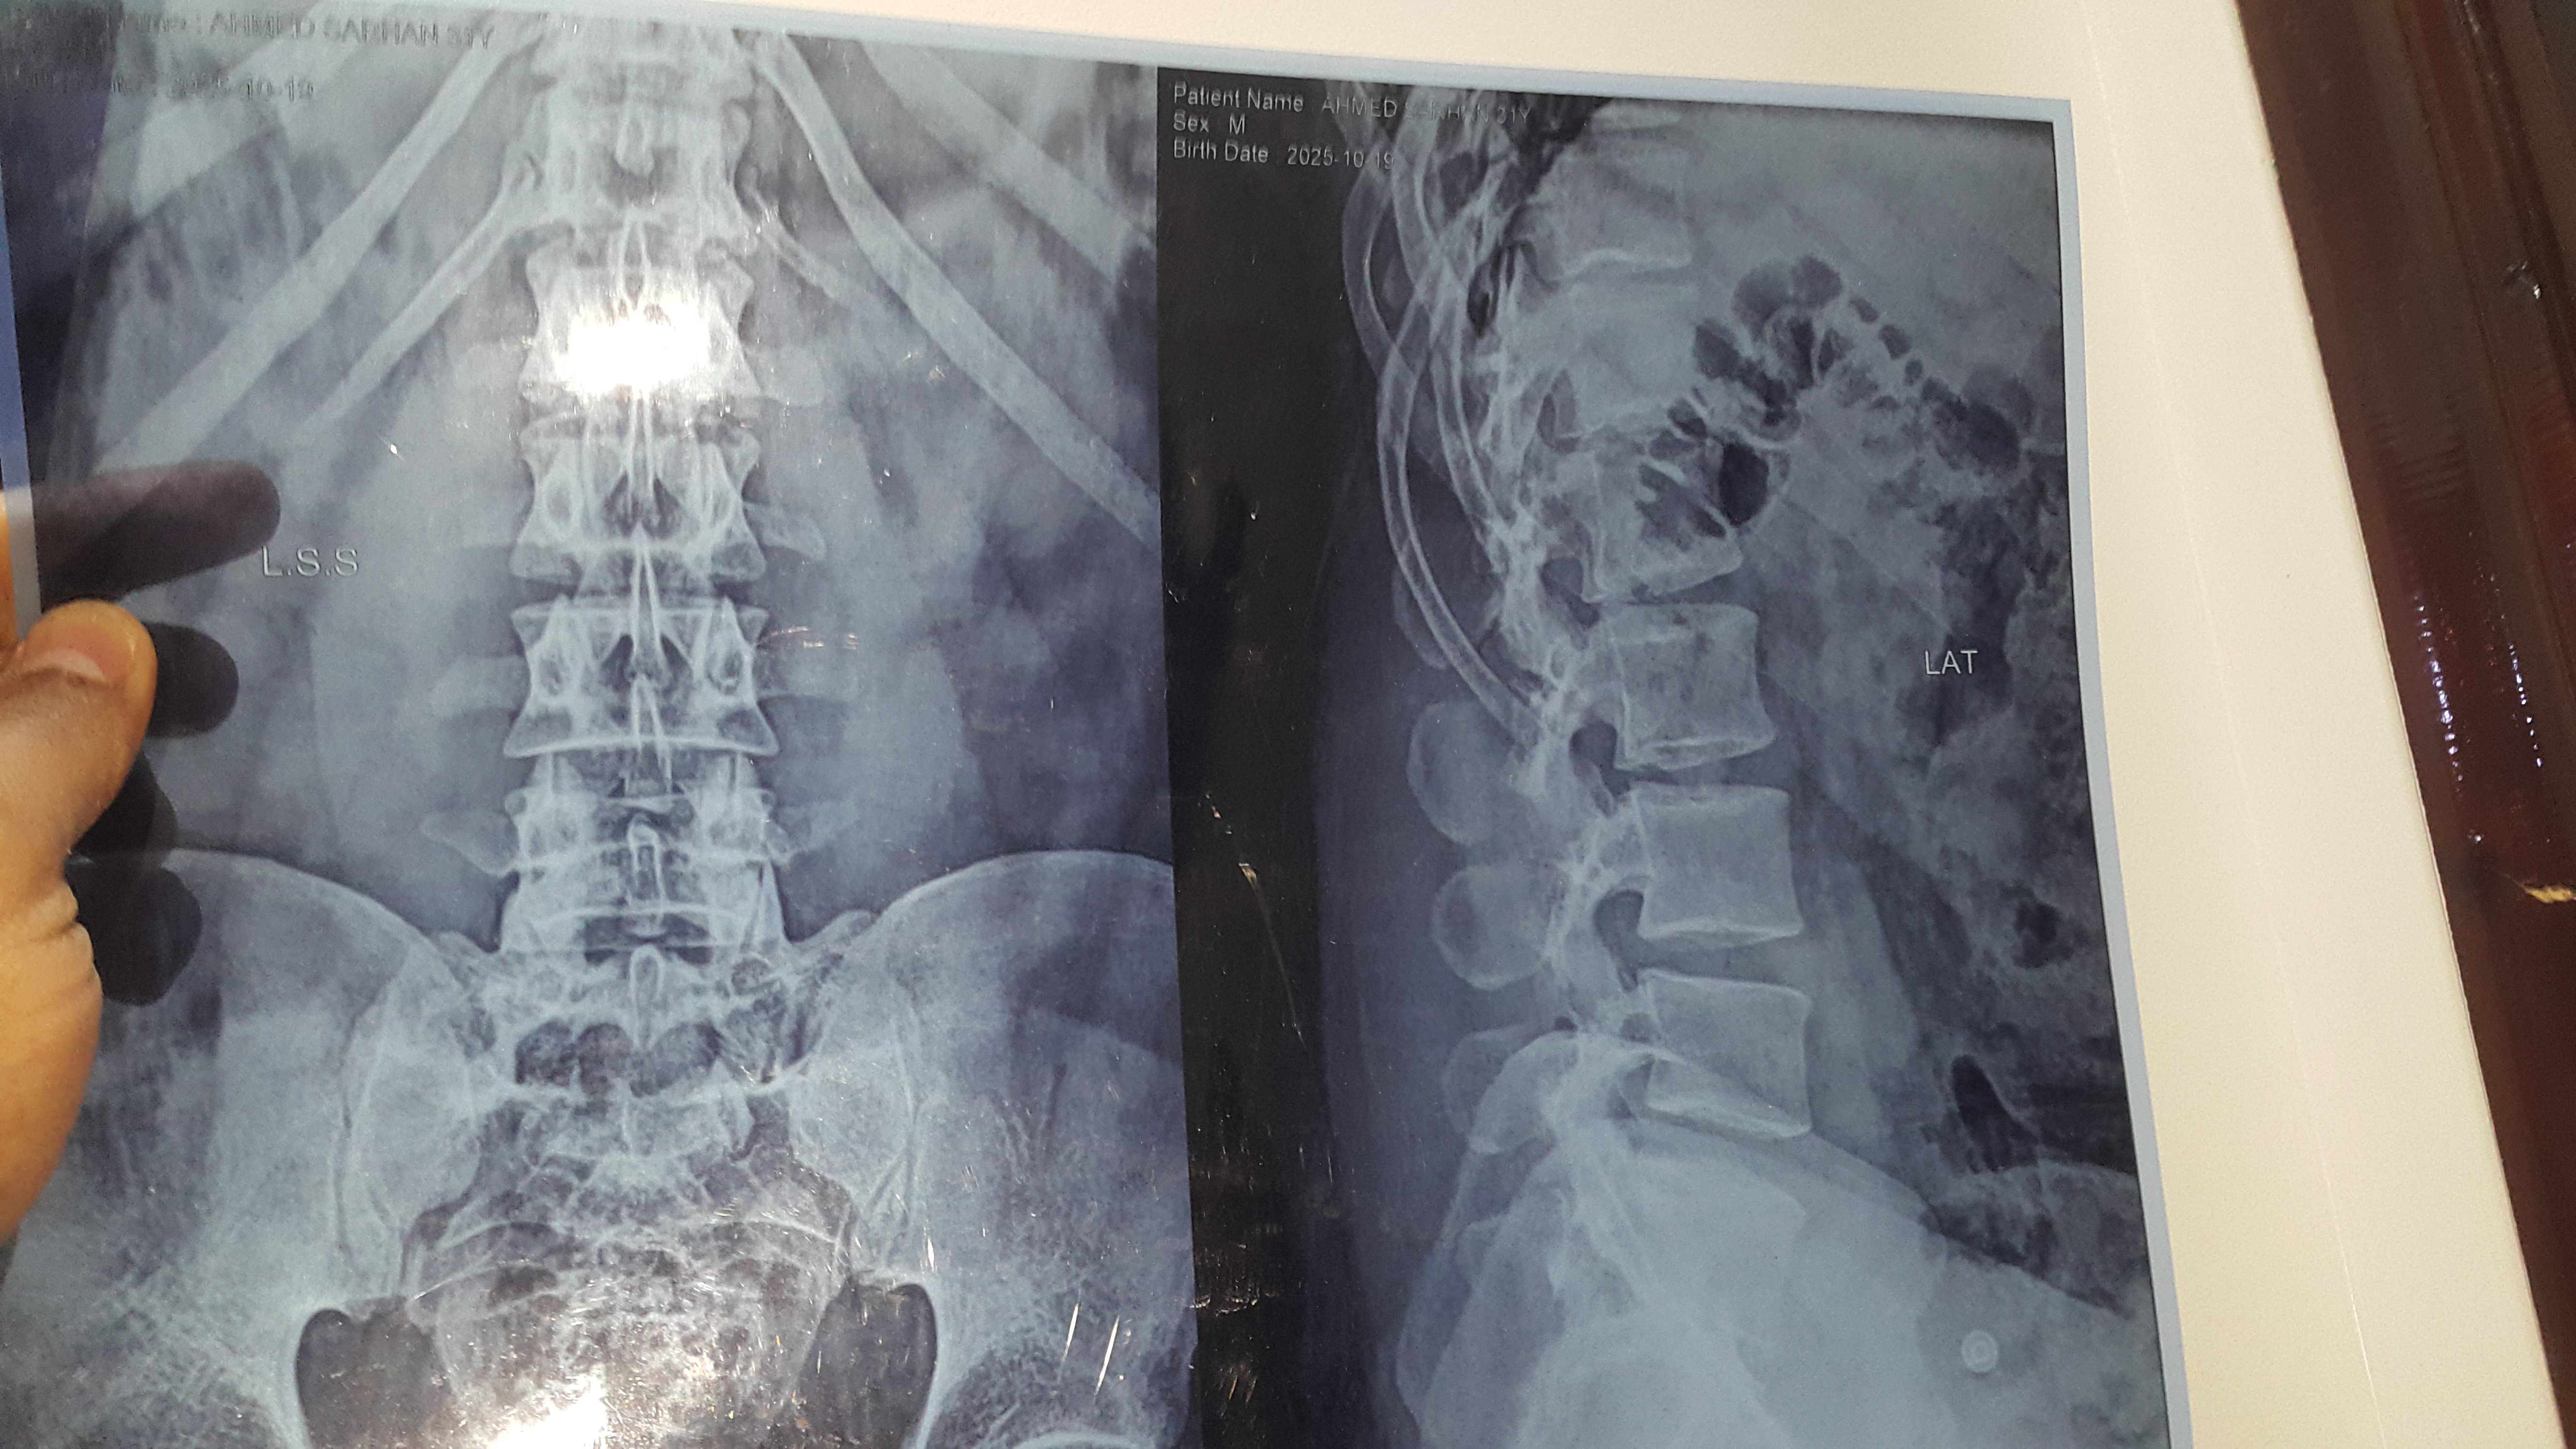

أشعر بالم في اسفل الضهر عند الانحناء لوقت قليل مثل الوضوء و الم في كعب القدم عند الوقوف لوقت قصير ووجع نشر حتي فوق الركبة مع أقل مجهود وصوت في مفاصل الركبتين والكتفين

الفحص السريري مهم عليك مراجعة طبيب روماتيزم لاجراء اللازم من تصوير وتحليل للدم ومن ضمنه نسبة الالتهاب ووظائف الاعضاء للاهميه CBC ESR CRP ALT Creatinine وكذلك تحاليل اخرى لمعرفة نوع الالتهاب وذلك حسب الفحص السريري وممكن رنين للمفصل الحرقفي وممكن تحليل HLA B27 حسب مايراه طبيب الروماتيزم 0 2026-03-10T09:26:43+00:00 2026-03-10T09:26:43+00:00

الفحص السريري مهم عليك مراجعة طبيب روماتيزم لاجراء اللازم من تصوير وتحليل للدم ومن ضمنه نسبة الالتهاب ووظائف الاعضاء للاهميه CBC ESR CRP ALT Creatinine وكذلك تحاليل اخرى لمعرفة نوع الالتهاب وذلك حسب الفحص السريري وممكن رنين للمفصل الحرقفي وممكن تحليل HLA B27 حسب مايراه طبيب الروماتيزم